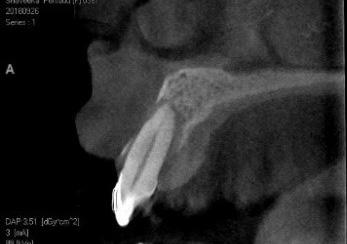

La paciente había comenzado un trata miento ortodóncico con un alineador transparente 6 meses antes de acudir a mi consulta. El objetivo del tratamiento orto dóntico era corregir una maloclusión cla se II de Angle con una moderada separa ción de los incisivos superiores, resalte (overjet) aumentado y proclinación de los incisivos superiores. Después de 6 meses de tratamiento, con cambios semanales de los alineadores creados por ordenador, la paciente desarrolló un absceso alrede dor del diente 12 y fue derivada a un endo doncista par drenar la lesión. Los dientes 11 y 12 se diagnosticaron como insalvables,

con profundidades de sondaje de 15 mm localizadas y movilidad de clase III. La tomografía computarizada de haz cónico (CBCT) y la radiografía periapical mostra ban pérdida de las paredes vestibular y palatina. No obstante, los dos dientes te nían un buen aporte sanguíneo, como se constató en la prueba de vitalidad pulpar. La paciente quería una segunda opinión y fue derivada a nuestra consulta.

| A Tomografía computarizada de haz cónico (CBCT) coronal o sagital que muestra la proximidad de la lesión periapical y el seno maxilar. | B Oclusión correcta antes del tratamiento. | C Plantilla quirúrgica 3D para guiar el acceso. | D Osteotomía con el Piezotome Cube (Acteon, EE. UU.) usando la punta SL1 después de elevar el colgajo. | D Osteotomía con el Piezotome Cube (Acteon, EE. UU.) usando la punta SL2 | F Preparación retrógrada sobre la raíz mesiovestibular con una punta Berutti (EMS, Suiza) e irrigación salina. | G Biocemento Bio C Repair (Angelus, Brasil) aplicado en el conducto mesiovestibular. | H Fotografía con el microespejo de 3 mm para comprobar la obturación retrógrada en la raíz distovestibular del segundo molar derecho superior. | I Geistlich Bio-Oss® Small 0,5 g. (Geistlich Pharma AG, Suiza) en el sitio quirúrgico. | J Cavidad quirúrgica rellenada con Geistlich Bio-Oss® Small. | K Membrana Geistlich Bio-Gide® 25 × 25 mm usada para cubrir el injerto. | L Radiografía final después de la cirugía.